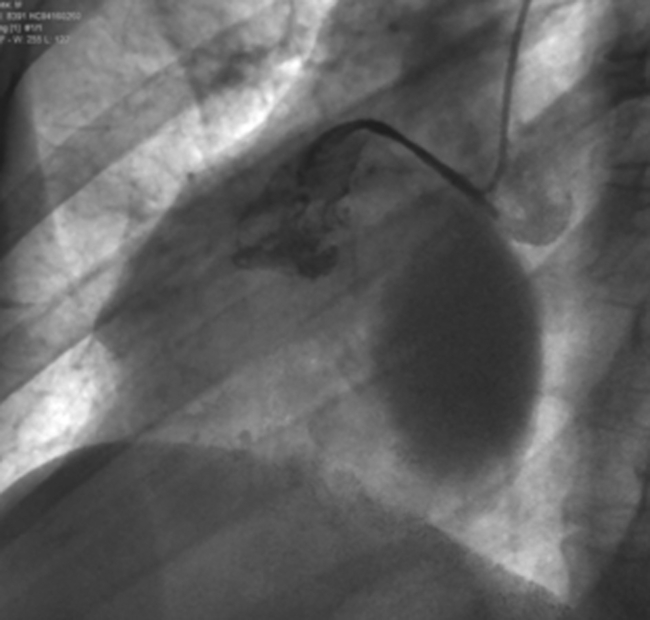

La cinecoronariografía demuestra la presencia de enfermedad ectásica difusa en arteria coronaria izquierda y confirma la presencia de un aneurisma gigante en arteria coronaria derecha. En la Figura 2, se puede observar la fuga de contraste desde la arteria coronaria derecha hacia el interior del aneurisma.

Coronariografía. Se observa la fuga del material de contraste desde la arteria coronaria derecha.